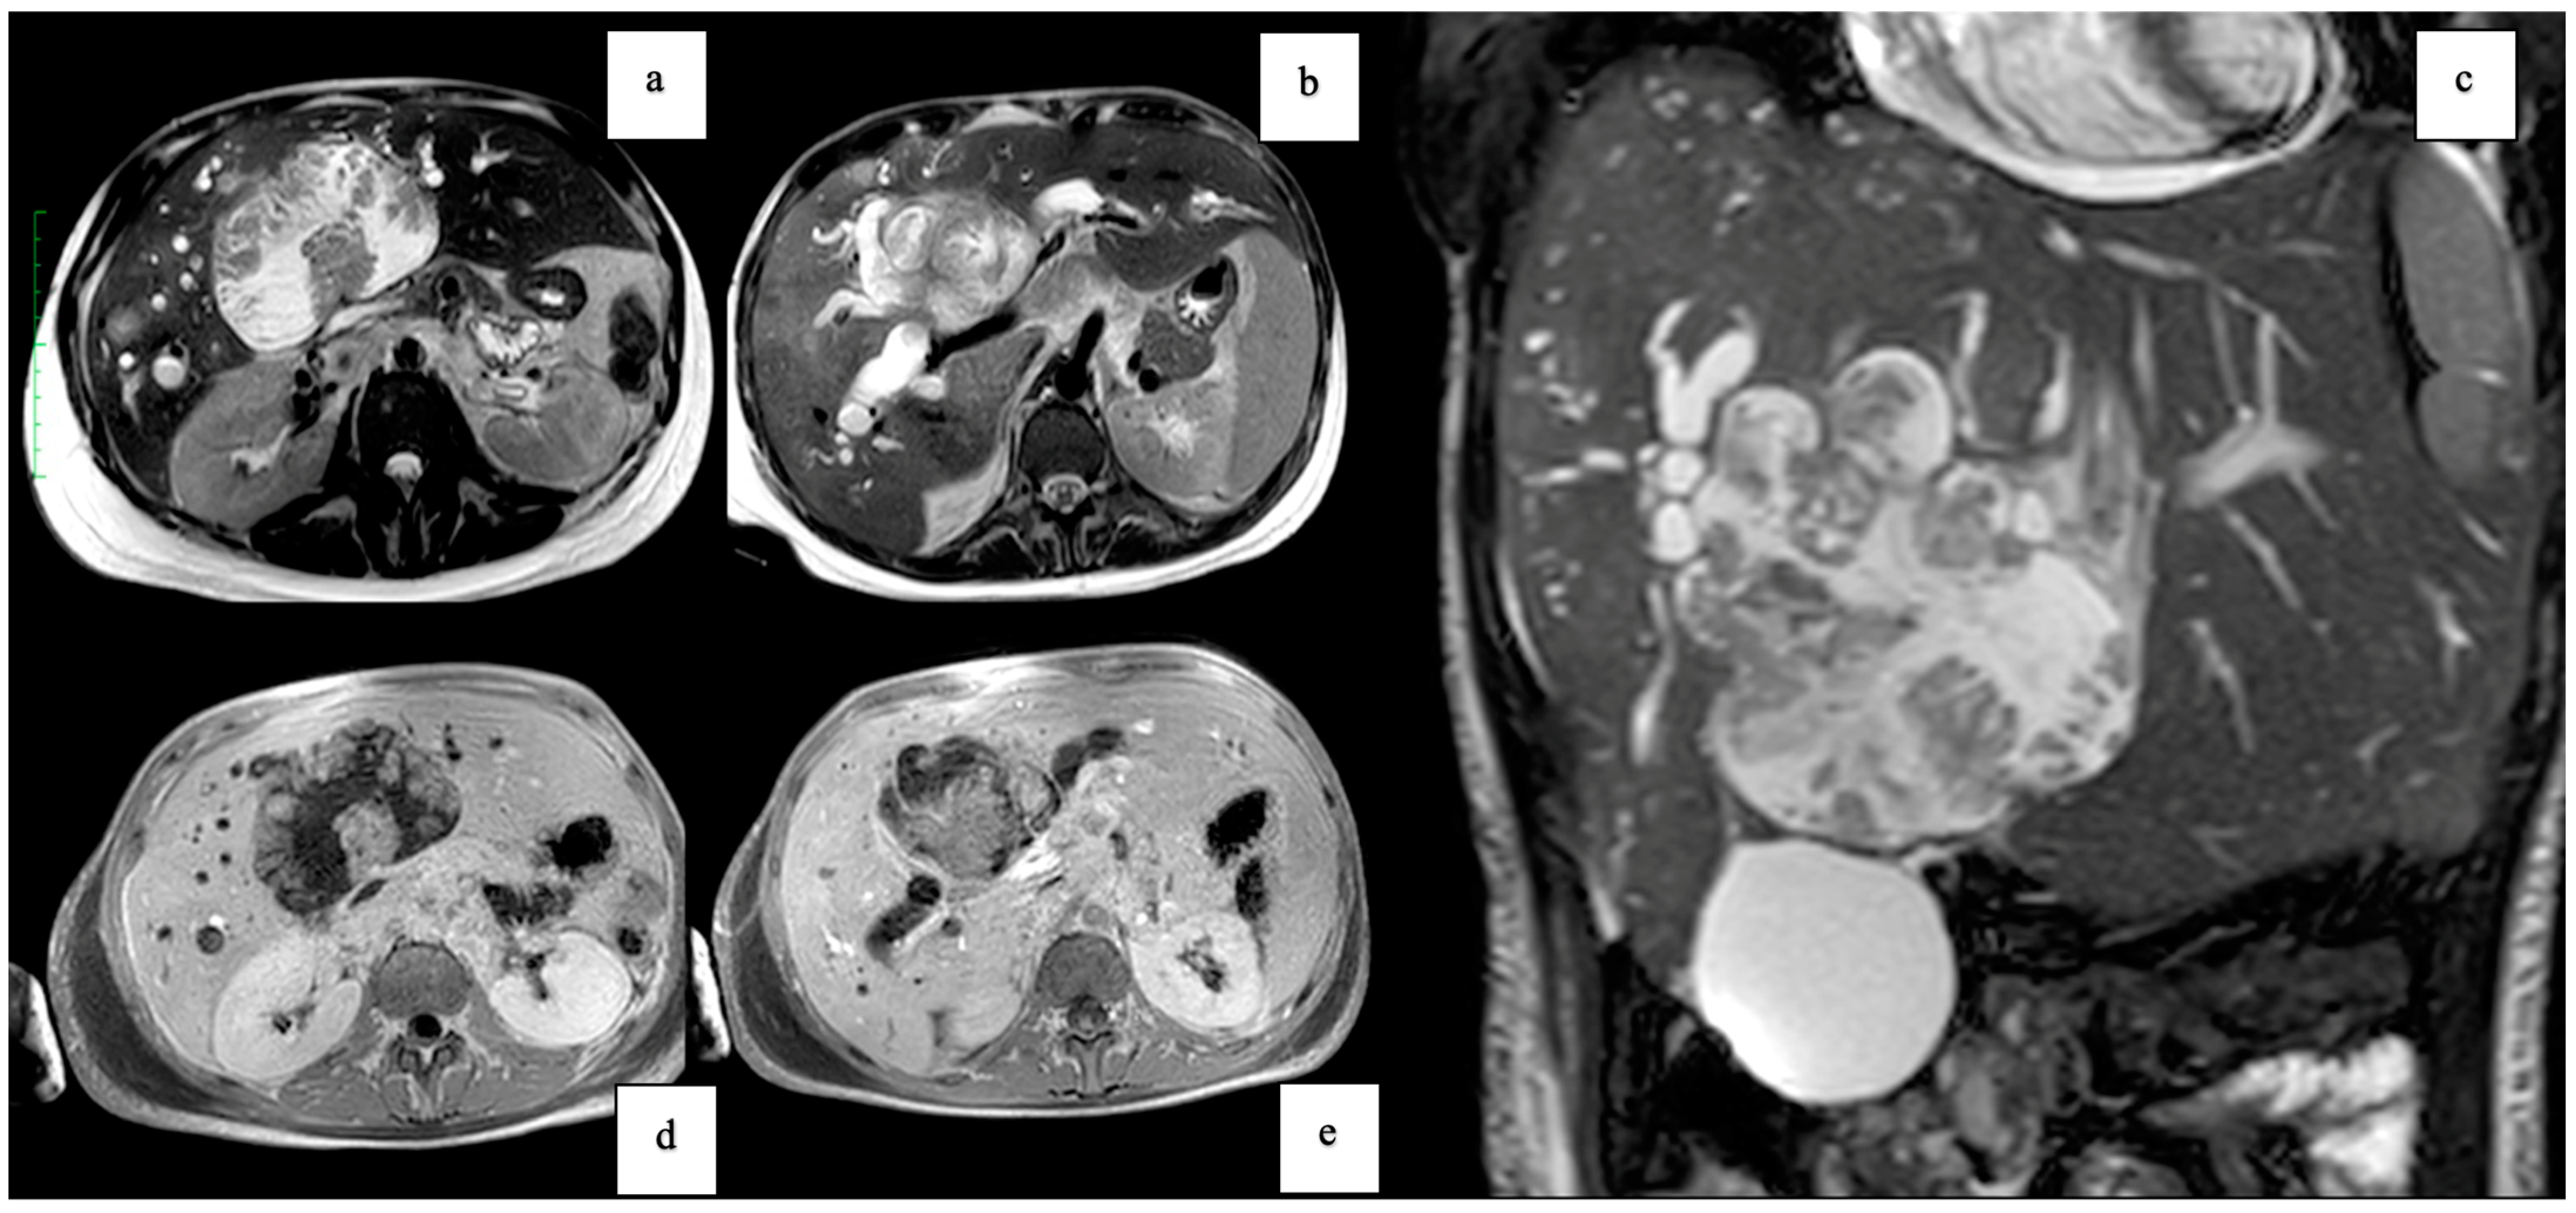

| Clinical Presentation | Incidental discovery of an 8 × 8 × 9 cm hepatic cyst | Presented with dyspnea, vomiting, jaundice, fever |

| Diagnostic Methods | MRI, MRCP, ERCP, histopathological examination | CT, MRI, laparoscopic liver biopsy, histopathological examination |

| Tumor Characteristics | Large cystic mass, thin walls, internal septa, papillary projections, enhancing solid components | Large lesion in left hepatic lobe, hyperintensity in T2-weighted images, restricted diffusion, contrast enhancement |

| Histopathological Findings | IPNB with foci of adenocarcinoma, oncocytic appearance, varying degrees of dysplasia, mucus within cyst | Adenocarcinoma with papillary clear cell and mucinous appearance, gland ectasis, cystic or pseudocystic aspects |

| Follow-up and Outcome | Initial recurrence-free survival for 8 years, recurrence treated with left hepatectomy, patient alive at 33 months post-second surgery | Disease progression despite aggressive management, patient died from hepatic failure |